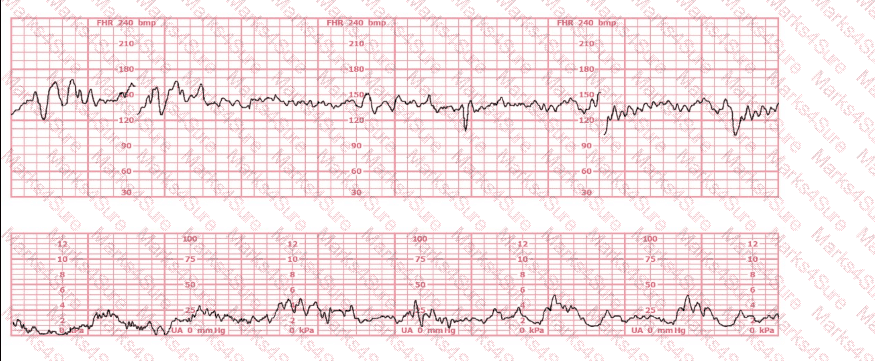

The decelerations seen in the fetal monitoring tracing shown are best described as: